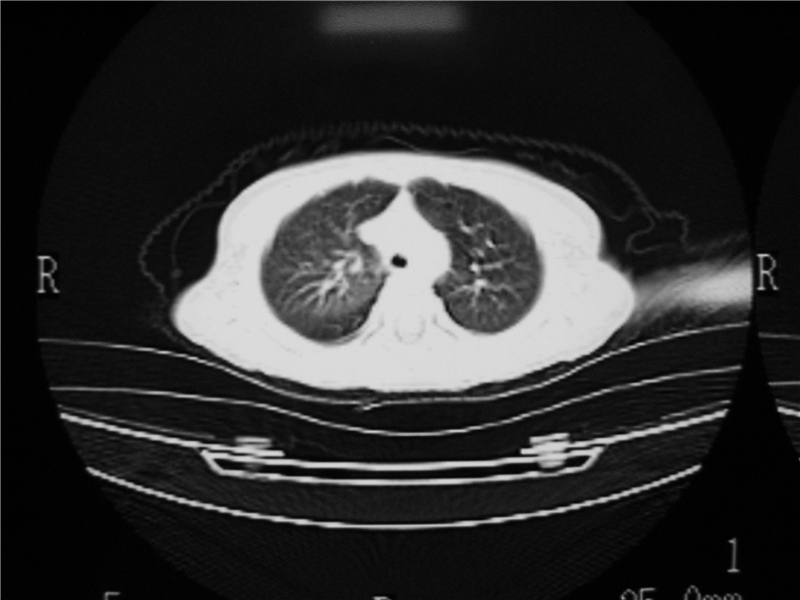

阻塞性肺炎及膨胀不全

摄吸气及呼气相对比片,本例为有肺中叶阻塞性炎症、不张,右肺下叶阻塞性炎症。

结合临床考虑支气管异物并阻塞性肺炎、肺不张。